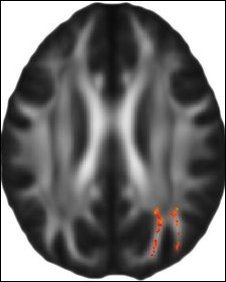

Este resultado es válido desde un punto de vista neurológico ya que se demostró un incremento en la plasticidad cerebral tras el entrenamiento en el área específica del cerebro encargada en la rotación mental, el surco intraparietal.